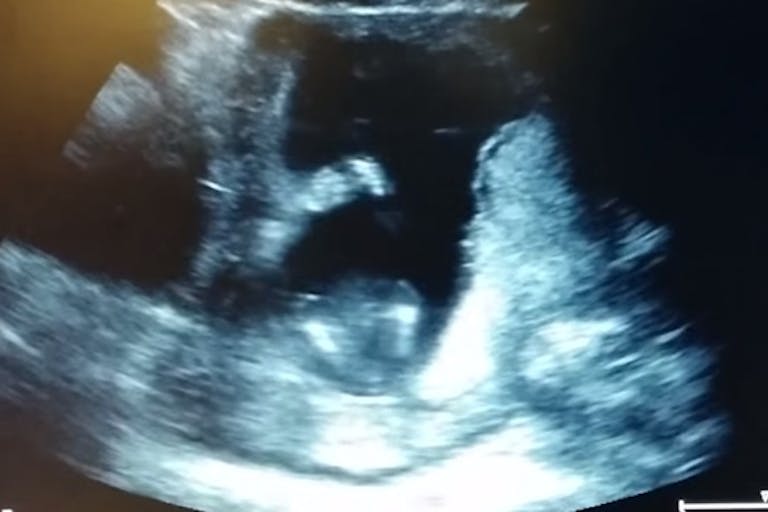

Jen Cardinal, a mother from Olympia, Washington, recently uploaded an ultrasound video of her 14-week-old preborn child. What makes this video amazing is that her preborn baby is clapping in the womb. The short video has gone viral since its first release.

Cardinal told TODAY News that the first three claps were “very real.”

“We went for an ultrasound. Our baby clapped two or three times. We gasped, laughed. Doctor said, ‘Let’s sing a song.’ He rewound and replayed it to us singing, so it looks like the baby is clapping. Great fun.”

Cardinal shared her exciting and special moment with the world. This video is evidence that preborn children are unique human beings, worthy of celebration and deserving of protection.